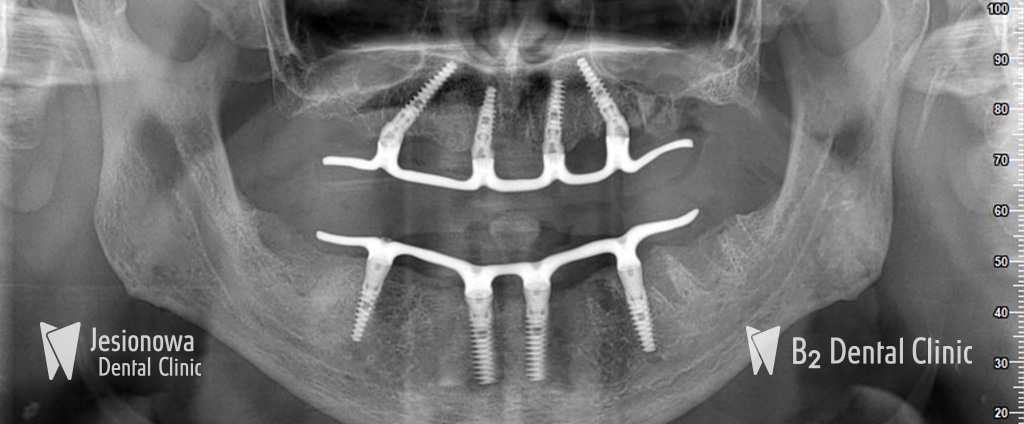

All-on-6 to metoda leczenia bezzębia polegająca na zastąpieniu brakujących zębów przy użyciu pojedynczego mostu mocowanego na stałe, obejmującego cały łuk zębowy przy użyciu 6 implantów zębowych i natychmiastowego ich obciążenia.

Zabieg podnoszenia zatok szczękowych przy zastosowaniu metody All-on-6 nie jest konieczny. Specjalne pochylenie 4 implantów zapewnia odpowiednią stabilizację w łuku zębowym oraz ominięcie zatok szczękowych.

Na tym etapie wszczepiamy 6 implantów do których zostanie przymocowana stała praca protetyczna. Zabieg jest całkowicie bezbolesny, a jego czas trwania wynosi średnio 90 min (bez dodatkowych zabiegów regeneracyjnych kości).